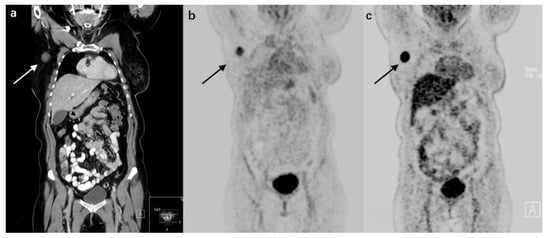

The chemokine receptor CXCR4 is expressed in many breast cancers, and has an important role in the migration, invasiveness, metastasis, and proliferation of tumors []. Several CXCR4 inhibitors or antagonists, such as AMD3100, Pentixafor, and T140, have been radiolabeled and used to image CXCR4 in small animals [,]. To evaluate the use of [68Ga]Pentixafor in detecting breast cancer, 18 patients underwent [68Ga]Pentixafor PET/CT or PET/MR, including 13 patients with a first diagnosis of breast cancer, four patients with recurrent disease after primary breast cancer, and one patient with axillary lymph node metastasis of unknown primary []. Nine of the 13 primary tumors were visually detected with [68Ga]Pentixafor, and all 5 metastases could be visually identified. Eight of them (4 recurrent breast cancer patients and 4 primary breast cancer patients) additionally received an [18F]FDG-PET within 2 weeks after administration of [68Ga]Pentixafor. Higher SUVmax of [18F]FDG were observed in all cases, compared with [68Ga]Pentixafor (mean SUVmax of 16.2 vs. mean SUVmax of 3.6; p < 0.05).(Figure 2) This study did not reveal any significant correlation between [68Ga]Pentixafor uptake and breast cancer prognostic factors (ER, PR, or HER2 status), proliferation index, or tumor grade. Moreover, [68Ga]Pentixafor uptake seemed to vary with histological tumor types. Since CXCR4 signaling mechanistically drives ER-positive breast cancers to metastatic and endocrine therapy-resistant phenotypes, PET imaging with [68Ga]Pentixafor might play a role in providing spatiotemporal information over the course of endocrine therapy [].

Figure 2.

A 67-year-old patient with a nodal recurrence at 22 months after treatment from primary breast cancer. (a) Coronal CT reconstruction shows a contrast-enhancing lymph node metastasis with a diameter of 2.1 cm in the right axillary region. (b) The lesion is visually detectable on [68Ga]Pentixafor-PET (SUVmax = 4.0). (c) The lesion has a significantly higher [18F]FDG uptake (SUVmax = 24.4). (Reprinted from Ref. []).